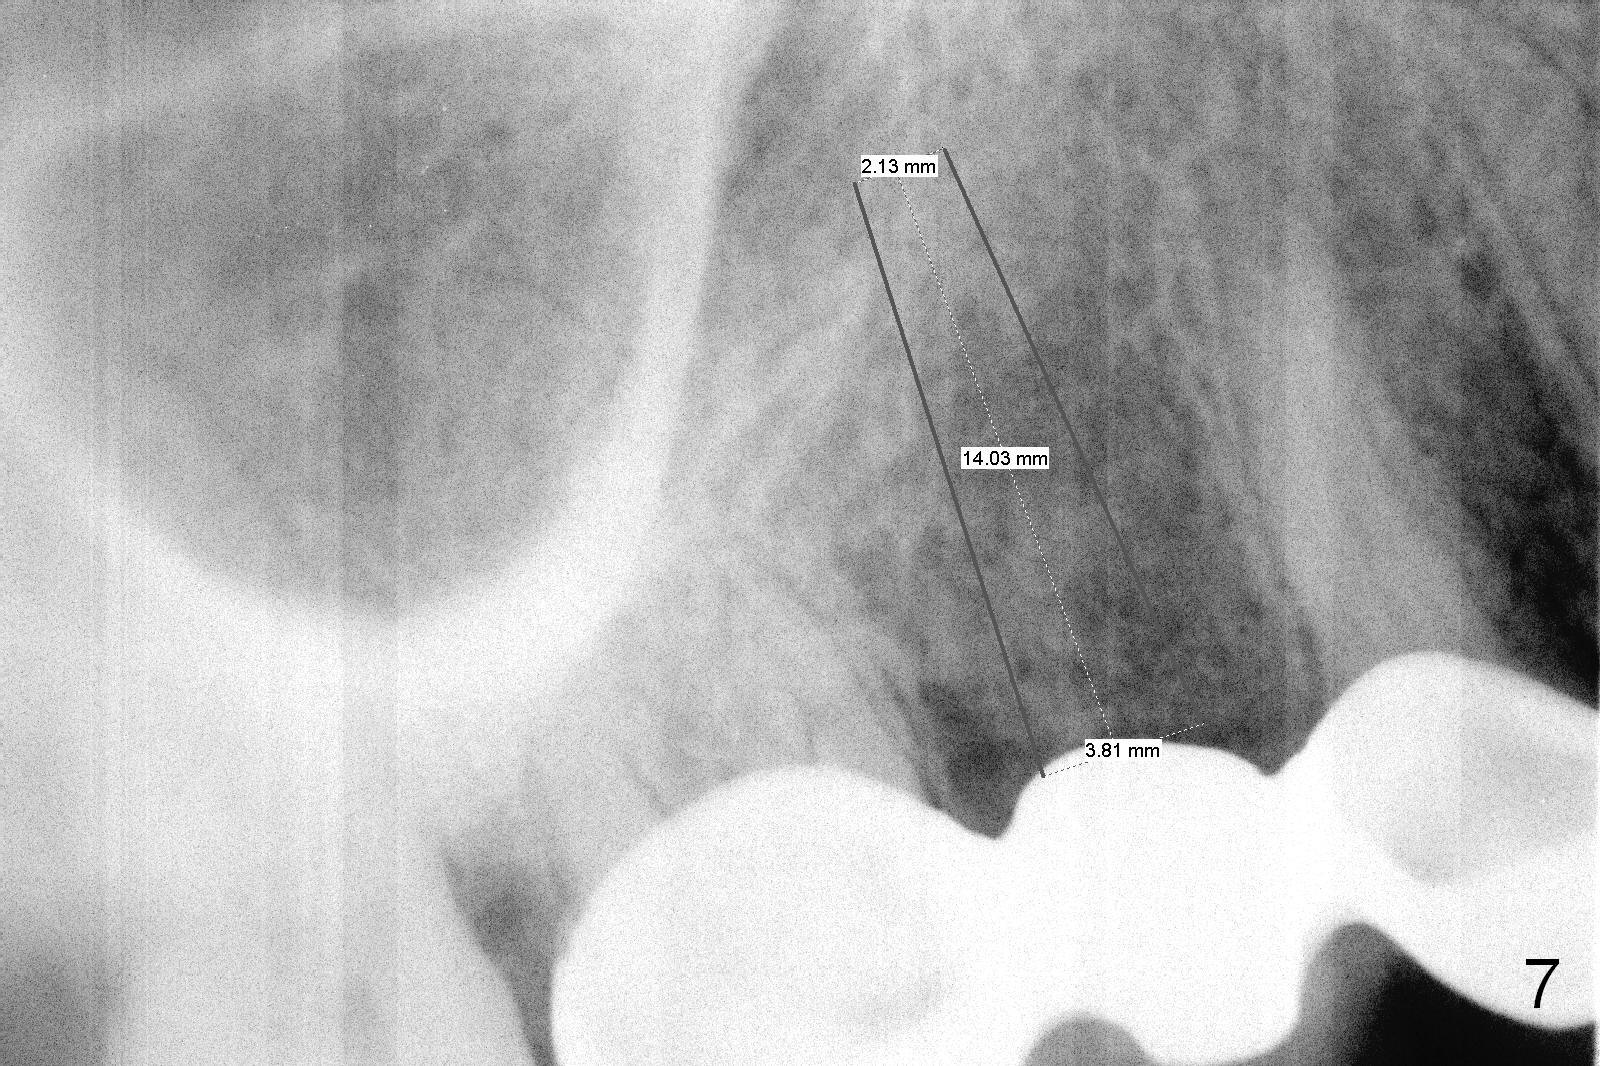

Ms. Li, a 34-year-old lady, had the upper right fixed partial denture made by an unlicensed dentist in California 10 years ago (Fig.1: #3-5). The gingival margin palatal to the retainers is erythematous (Fig.1 arrows). The patient's chief complaint is gum bleeding. The retainer at #3 is over-contoured buccopalatally (Fig.1, as compared to #14 in Fig.2), while the one at #5 is over-contoured buccopalatally and mesiodistally (compare to #12 in Fig.2). Panoramic X-ray (Fig.3), bitewing (Fig.4) and periapical film (Fig.5) all confirm that the bridge is over-contoured and that the retainers #3 and 5 have open margin (Fig.4 arrowheads). To improve oral hygiene and save the abutment teeth #3 and 5, it is in the patient's best interest to remove the bridge, place an implant at #4 and fabricate single-unit crowns at #3 and 5. Three to four months later, pyogenic granuloma develops between #4 and 5 (Fig.6 *) with generalized gingival erythema apically. The pontic at #4 and the retainer at #5 are to be removed first. An implant will be placed at #4 (Fig.7) with conjoined provisional at #4 and 5. The initial depth of osteotomy is 13 mm with Sinus Master Kit.